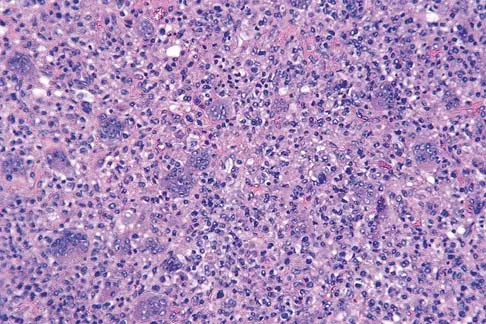

A 19-year-old girl has had pain and swelling in the right ankle for the past 4 months. She denies any history of trauma. Examination reveals a small soft-tissue mass over the anterior aspect of the ankle and slight pain with range of motion of the ankle joint. The examination is otherwise unremarkable. A radiograph and MRI scan are shown in Figures 45a and 45b, and biopsy specimens are shown in Figures 45c and 45d. What is the most likely diagnosis?

Explanation